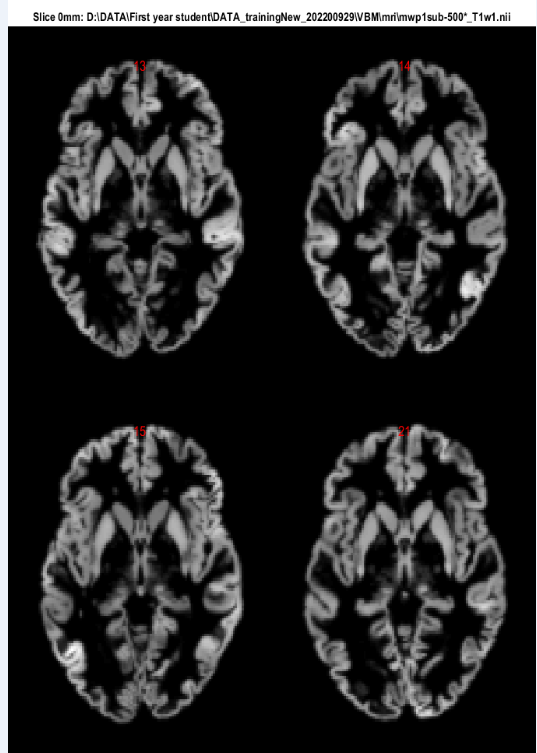

分割结束之后,我们需要对数据进行质量检测,为下一步统计分析做准备。关闭分割界面,回到cat12操作界面,下拉 Data Quality,选择Slice Display

进入界面可以选择四个测试样本的灰质mwp1-或白质mwp2-的.nii文件,点击proportional scaling选择yes

点击运行之后就可以在Matlab自动弹出的figure窗中查看分割结果,如下图所示(灰质分割结果):